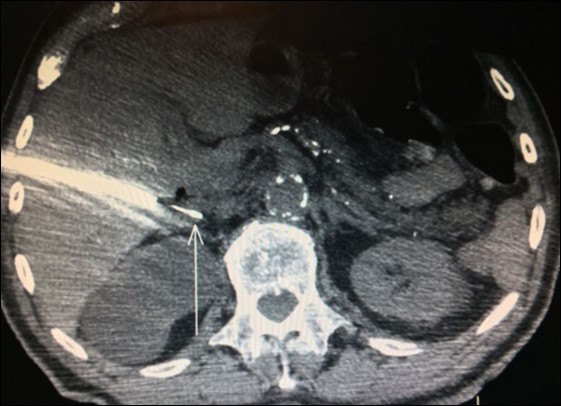

Nevertheless, in another study, only 28 out of 39 (71.8%) patients who underwent adrenalectomy for suspect adrenal tumor by FDG-PET/CT confirmed metastasis. Ten of those were benign adenoma and one was a non-functional pheochromocytoma29. Thus, FDG-PET/CT produced an unexpected high rate (28.2%) of false-positive results in this trial. Despite benign adenoma may mimicking metastasis and produce a positive preoperative FDG-PET/CT, history of primary lung malignancy and SUV max >2.65 were more commonly associated with metastasis in this paper (Figure 2).

Figure 2.PET-CT with high uptake on right adrenal